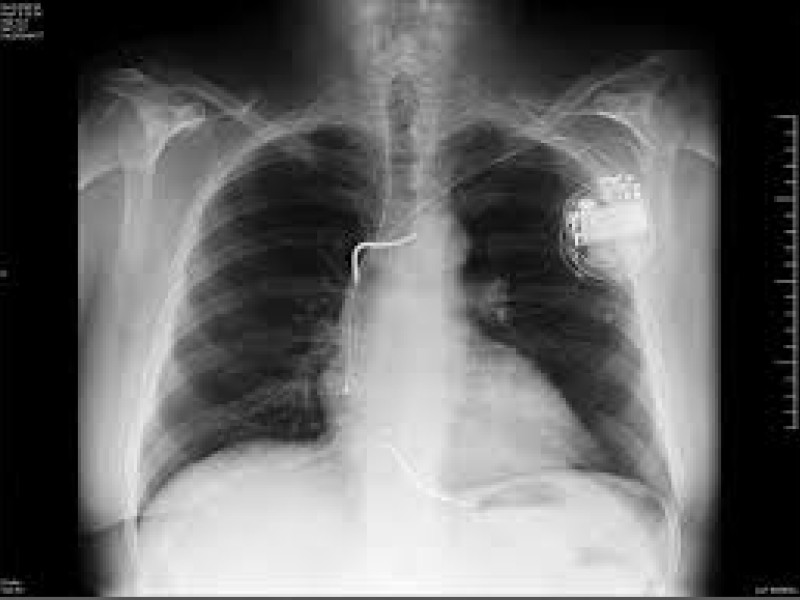

Desfibrilador automático implantable (DAI) visto a través de una radiografía

Un desfibrilador automático implantable (DAI) es un pequeño dispositivo que se coloca bajo la piel del pecho y se conecta al corazón mediante unos electrodos. Su misión es vigilar de forma continua cada latido y actuar en caso de que aparezca una arritmia peligrosa.

El funcionamiento comienza con la monitorización permanente. El DAI registra el ritmo cardíaco y es capaz de reconocer si el corazón late demasiado rápido, demasiado lento o de manera caótica. Cuando identifica una alteración que pone en riesgo la vida, entra en acción. Si la arritmia es rápida pero aún puede controlarse, primero intenta corregirla con una estimulación antitaquicardia: pequeños impulsos eléctricos que buscan devolver al corazón un ritmo ordenado. Si esa medida no es suficiente o el corazón entra en fibrilación ventricular, el dispositivo libera una descarga más potente, parecida a la de un desfibrilador externo, pero administrada desde dentro del organismo para reiniciar la actividad cardíaca.